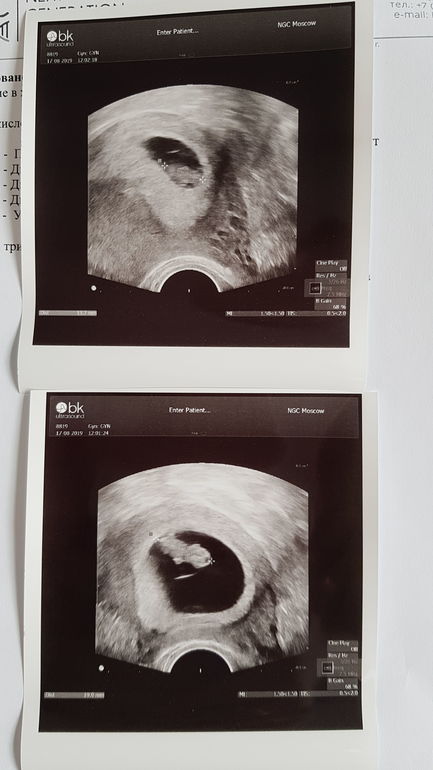

На втором фото, судя по методу Рамзи, мальчик. А на первом, кмк, девочка))) голосую за королевскую двойню! 💕

Растите малышата 🤗🤗

Мы растём

Мы растём